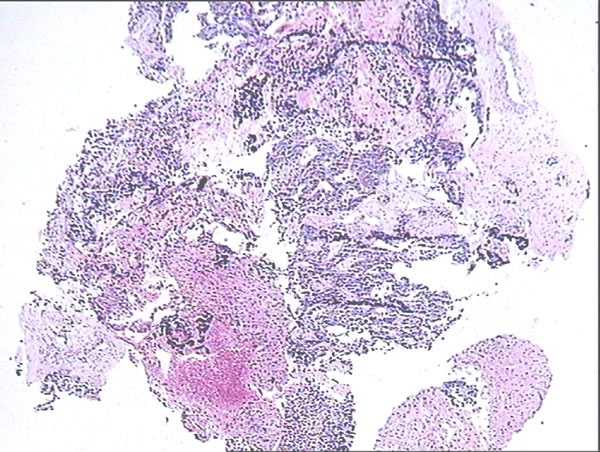

From Jan 2012 to Jan 2014, 62 CRLM patients underwent clinical treatment of CRLM at our department. Firstly, the liver biopsy was carried out before the treatment, and then the type of pathological samples were defined by two sophiscated pathology doctors (Figure 1). After the diagnosis of CRLM, MWA was conducted in 45.2% (28/62) of CRLM patients as described above and shown in Figure 2. Patient demographics are shown in Table 1. 34 cases of patients underwent hepatectomy. In the patient cohort, 46.8% (29/62) of all patients were female, and the median age was 60 years. Nearly all patients received either preoperative and/or postoperative chemotherapy. In addition, single tumor account for 64.5% of all tumors, and showed no differences from multiple tumors in both groups (p = 0.973). The pathological type of most tumors was low/mild differentiated in MWA (85.7%) and resection (82.4%) group. Most importantly, there was no significant difference between treatment and control cohort in tumor size (p = 0.487), liver metastasis time point (p = 0.368), Child-Pugh (p = 0.652) or pathological type (p = 0.884). These results suggested that the baselines in both group has no differences.

Figure 1: Pathological identification of CRLM. HE staining was conducted, and two pathological experts identified the relevant pathological type of liver biopsy tissues.